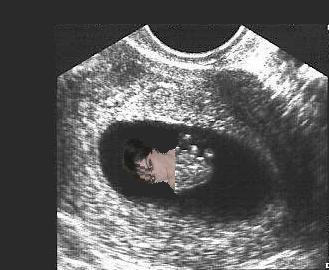

We had a little scare on Friday and I was given an early ultrasound. Fortunately, everything looked good. Baby measured just right for it's age (about 8wks) at 1.5cm and the little heart was beating along at a steady 145bpm (also very good). Everything else looked good as well. I thought I would include a picture for anyone interested.

baby2.jpg

baby2.jpg [ 19.12 KiB | Viewed 4702 times ]